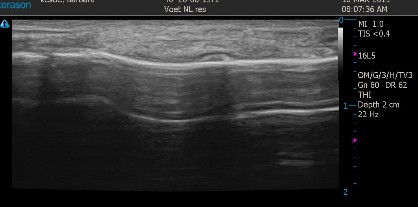

Op onze locatie in Nieuwkoop beschiken we over een echo apparaat. Hiermee is het mogelijk de voet ook van binnen te bekijken.

Op een echo kun je bijvoorbeeld bekijken of er sprake is van een peesontsteking, een hielspoor en of de pijn in de voorvoet mogelijk wordt veroorzaakt door een geirriteerde zenuwknoop(Mortons neuroma). Ook voor het aantonen en/of volgen van het genezingsproces bij een stressfractuur kan de echo worden ingezet.

Zo kan nog nauwkeuriger een diagnose worden gesteld of het verloop van de behandeling worden gevolgd.